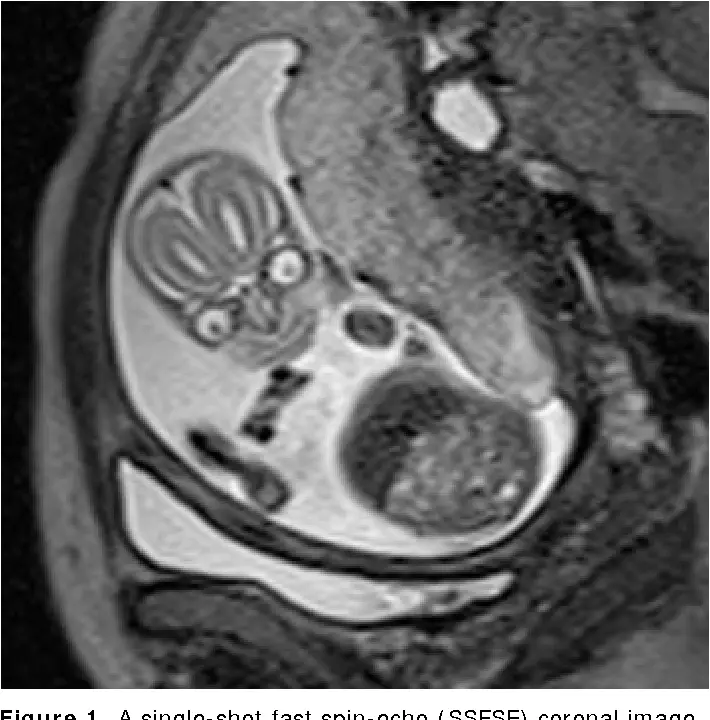

In what is probably the creepiest image on the internet comes a lesson as to why we don’t make pregnant women go through a magnetic resonance imaging (MRI) machine.

You might be asking why the feotuses look like goopy jack-o-lanterns or that creepy thing from Mars Attacks, but there’s actually a very simple reason.

"MRI makes it very easy to differentiate between different types of soft tissue found in the body and we are mostly soft tissue. Remember, we are mostly water," Moody said. "One of the primary features of these images are the substantial signal differences between the eyes, brain, nose, and the rest of the face."

To do it, Moody explained how they image mothers, noting: "We place a coil of wire around patients as the protons in their body rotate and we use that coil to measure the energy released by the rotating protons as a current. That current is then converted into an image and different tissue types will look differently from one another based on how differently their protons behave (how quickly they lose energy)."

It gives a super detailed view of a baby’s brain before they are born, in cases where they are worried about its development or need to double check things.

According to an article published by RSNA in its RadioGraphics issue, advances in magnetic resonance (MR) imaging have almost eliminated the need for fetal premedication, because they can now see clearly the baby in utero via their technology.